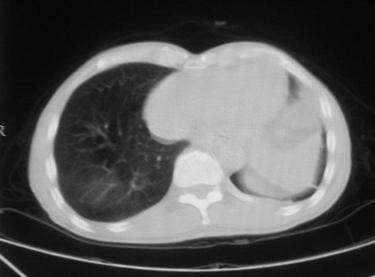

男,66岁,贲门ca术后一年,喝了5、6杯水了。怎么描述跟诊断啊